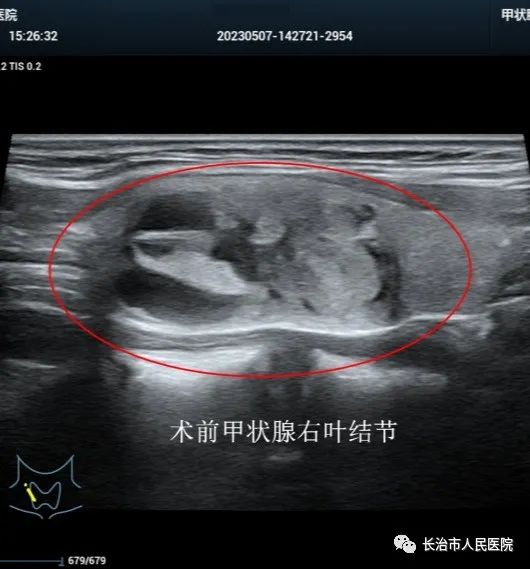

近年来,超声医学技术发展迅猛,尤其是介入超声的发展,迎来了超声从诊断到治疗的里程碑。介入超声以其针过无痕、精准微创等优势获得了临床及患者的认可。10cm大小的肝囊肿,16cm大小的肾囊肿,3cm大小的甲状腺良性结节,0.8cm大小的甲状腺恶性结节,无论其大小良恶,在崔教授精湛的操作技术下,在一根细针的舞动下,在“超声造影”等超声利器的助攻下,短短几分钟或十几分钟,病灶就被“解决”,患者体表只留下一个几乎看不到的针眼。一个巨大肾囊肿患者,术后当场在我院日间手术室门口蹦跳了几下,眉开眼笑,说感觉身体瞬间轻盈了许多。